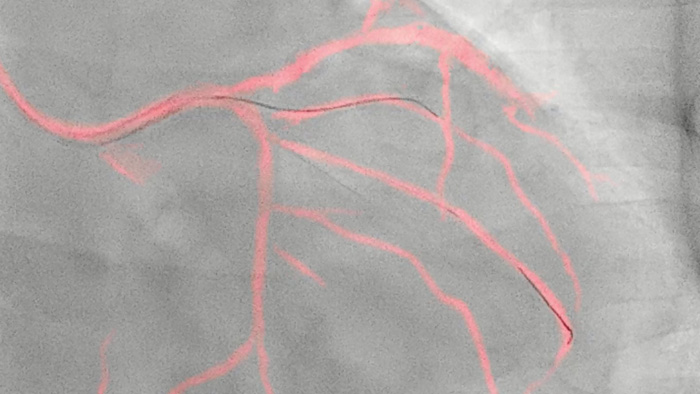

フィリップスの技術により、冠動脈の体動補正されたリアルタイムビューを作成します。ハイライト表示された冠動脈造影画像がライブ2D透視画像に重ねて表示され、カラーロードマップが作成、自動調整され、ワイヤやカテーテルの配置に関する連続的な視覚的フィードバックが提供されます。

iFRコレジストレーションはiFR、FFRの生理学的指標を血管造影にマッピングすることで、より包括的な診断、治療ガイダンスを可能にします。